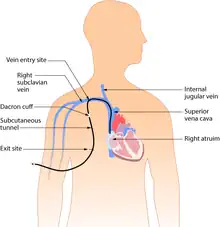

Subcutaneous or tunneled central venous catheter

Tunneled catheters are passed under the skin from the insertion site to a separate exit site. The catheter and its attachments emerge from underneath the skin. The exit site is typically located in the chest, making the access ports less visible than catheters that protrude directly from the neck. Passing the catheter under the skin helps to prevent infection and provides stability. Insertion is a surgical procedure, in which the catheter is tunneled subcutaneously under the skin in the chest area before it enters the SVC. Commonly used tunneled catheters include Hickman, and Groshong, or Broviac catheters and may be referred to by these names as well.

A tunneled catheter may remain inserted for months to years. These CVCs have a low infection rate due to a Dacron cuff, an antimicrobial cuff surrounding the catheter near the entry site, which is coated in antimicrobial solution and holds the catheter in place after two to three weeks of insertion.[28]